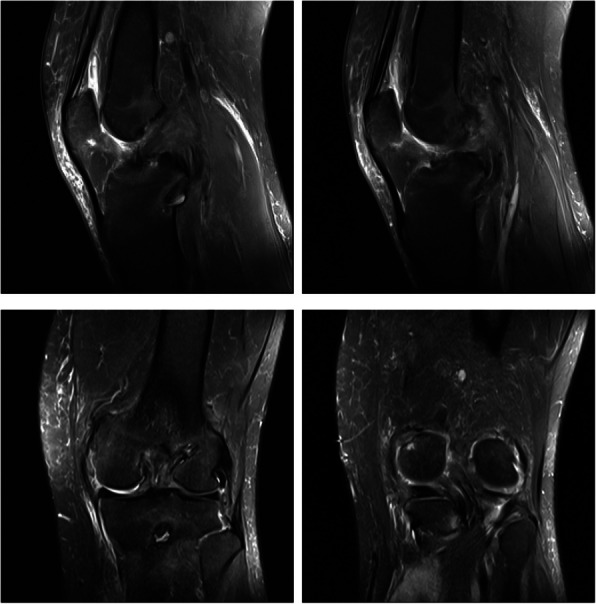

Septic arthritis or adult-onset still's disease: analyzing the causes of recurrent fever after arthroscopic combined anterior cruciate ligament and posterior cruciate ligament reconstruction: a case report.